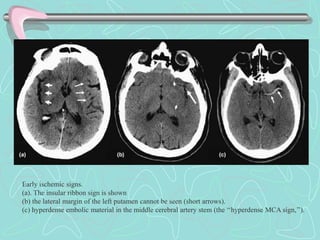

Early ischemic signs.

(a). The insular ribbon sign is shown

(b) the lateral margin of the left putamen cannot be seen (short arrows).

(c) hyperdense embolic material in the middle cerebral artery stem (the ‘‘hyperdense MCA sign,’’).